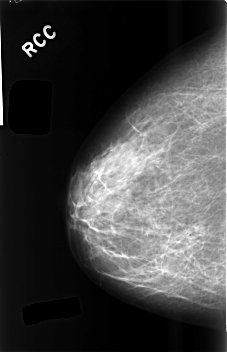

C_0489_1.RIGHT_CC

RIGHT_CC LINES 4576 PIXELS_PER_LINE 2944 BITS_PER_PIXEL 12 RESOLUTION 50 NON_OVERLAY